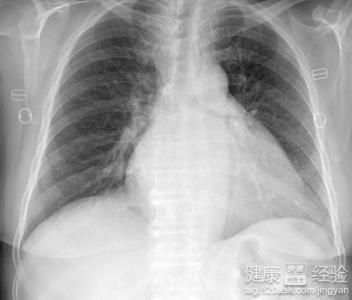

相信很多朋友對於風濕性心髒病都並不是十分的了解,那麼風濕性心髒病,主要是因為風濕熱的活動導致我們心髒瓣膜受到一定的損傷,而出現的一種疾病,我們也會稱之為是風心病。風濕性心髒病出現之後會造成患者肺部的水腫,還會引起右心衰竭,會經常出現咳嗽。那麼風濕性心髒病究竟是怎麼回事呢?我們下面來具體的了解一下,風濕性心髒病的原因。